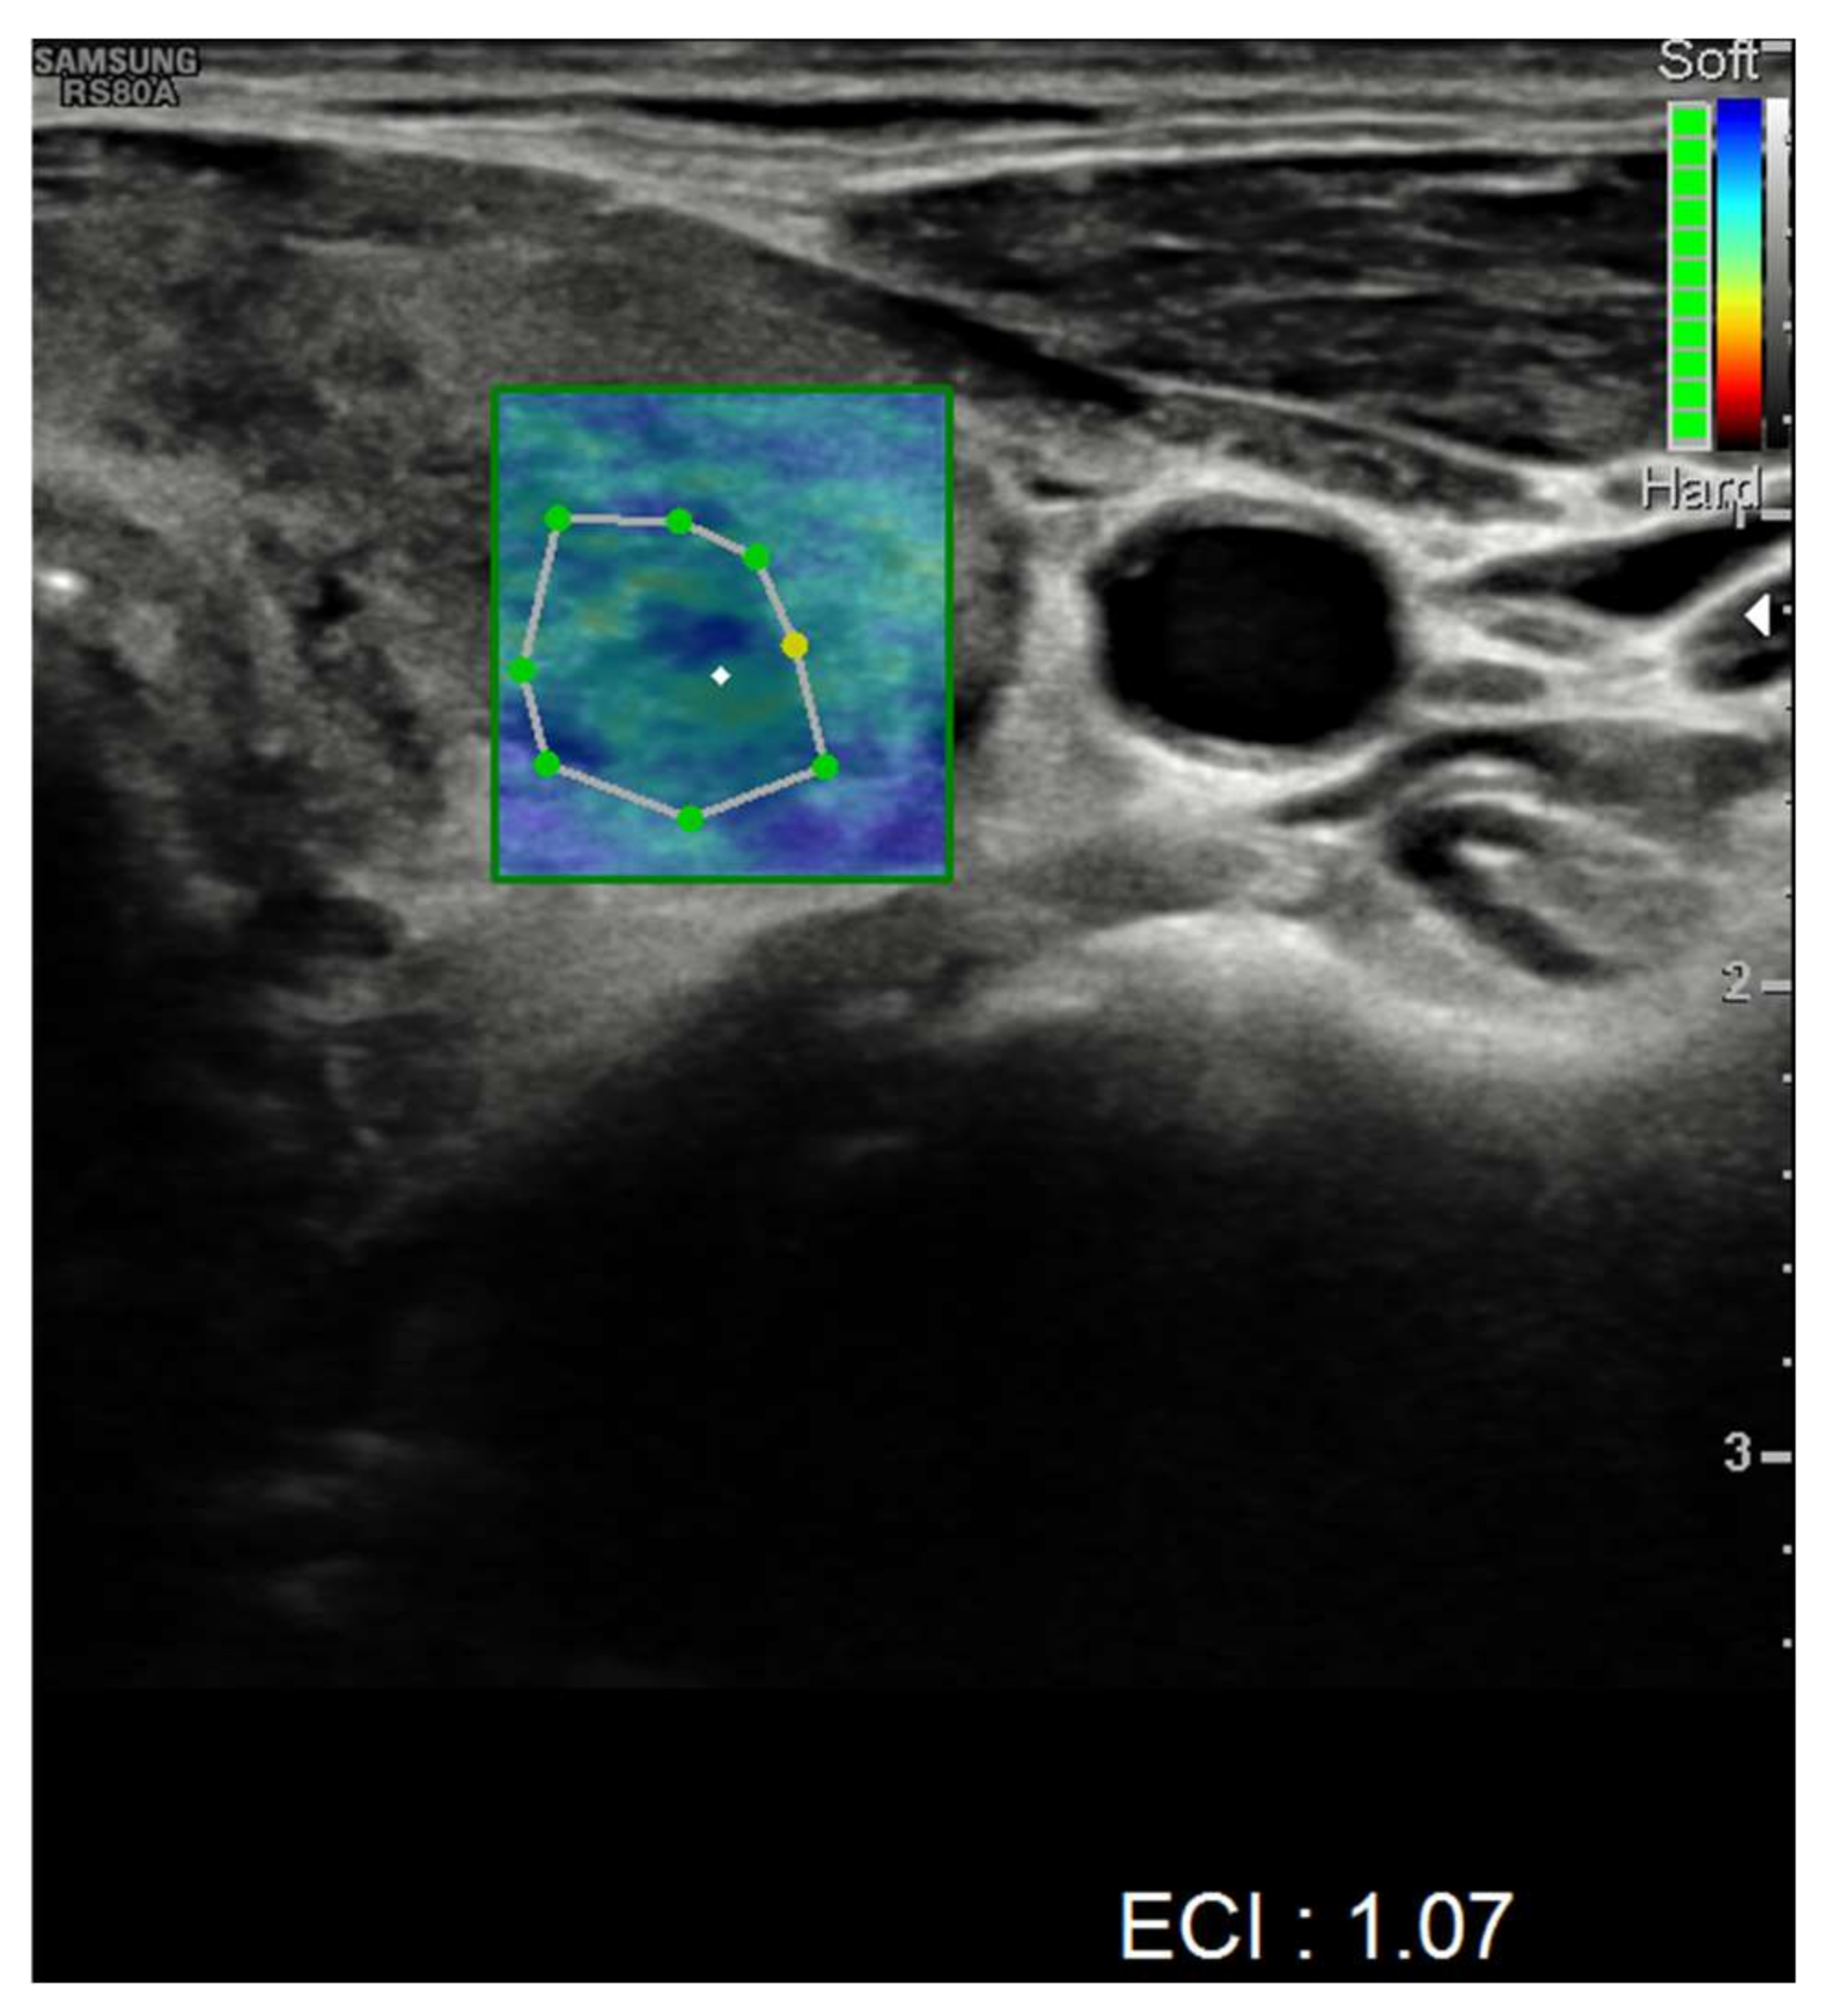

| Ultrasound findings at presentation | Asymmetric thyroid enlargement with two hypoechoic areas with no internal vascularity on right thyroid lobe | Diffuse thyroid enlargement with hypoechoic areas with heterogeneous echotexture and no evidence of increased vascularity | Diffuse enlargement of thyroid gland with hypoechoic nodules with hyperechoic shoots (micronodular pattern) without increase in vascularity | ||||||||||||||